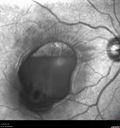

62 year old african american female with moderate chronic hypertension A few weeks ago she was at work and noticed a dark spot in the right eye. Since then it is not getting any better. She was out of town when it happened. VA OD: Dcc6’/200 Ncc20/400 VA OS: Dcc20/32 NccJ1

Macroaneurysm - Macular Hemorrhage - Branch Retinal Aterial Occlusion435 views62 year old African American female with chronic hypertension and vision loss for 2 weeks. VA is 20/40000000